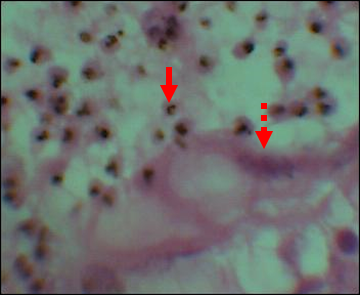

Overall (HIV+ and HIV-), 27.99% (82/293) of placentas showed no trace of malaria infection (Cat N). Category 1 lesions (Cat 1) were found in 19.45% (57/293) of placentas. Those of category 2 (Cat 2) were found in 29.01% (85/293) and lesions of category 3 (Cat 3) concerned 23.55% (69/293) of placentas. The lesions most frequently found in HIV+ mothers were those of Cat 2, 71/145, or 49.00% compared to 14/148, or 9.50% for HIV- mothers (OR=26.92; CI at 95%=11.10-67.60; p<0.0001). While Cat 3 lesions were more prevalent in HIV- mothers 46/148 (31.10%) vs 23/145 (15.80%), found in HIV+ mothers (OR=2.65; CI to 95%=1.15-6.21; p=0.020; (Table 4, Figures 1, 2, 3).

Figure 2 Histological image of category 1 showing Maternal RBCs parasitized in the EIV (solid arrow) and a Syncytiotrophoblast cell (dotted arrow). ET: x 40.